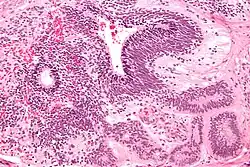

Yolk sac tumor

The ovarian yolk sac tumors, also known as endodermal sinus tumors, are accountable for approximately 15.5% of all OGCTs.[8] They have been observed in women particularly in their early ages, and rarely after 40 years of age.[9] The critical pathologic features are a smooth external surface and capsular tears due to their rapid rate of growth. A study consisting of 71 individual cases of ovarian yolk sac tumor provides evidence to the proliferation of the tumor. In one of the cases, the pelvic examination revealed normal activity until a 9 cm and 12 cm sized tumor was discovered 4 weeks later.[9] In another case, a 23 cm tumor was discovered in a pregnant woman who was monitored regularly and had normal findings until oophorectomy became essential.[9] Histologically, these tumors are characterized by mixed solid and cystic components.[1] The mixed solid components are characterized by a soft gray to yellow solid components accompanied with significant hemorrhage and necrosis. The cysts are approximately 2 cm in diameter and populated throughout the tissue which results in giving the neoplasm a ‘honeycombed appearance’.[1]